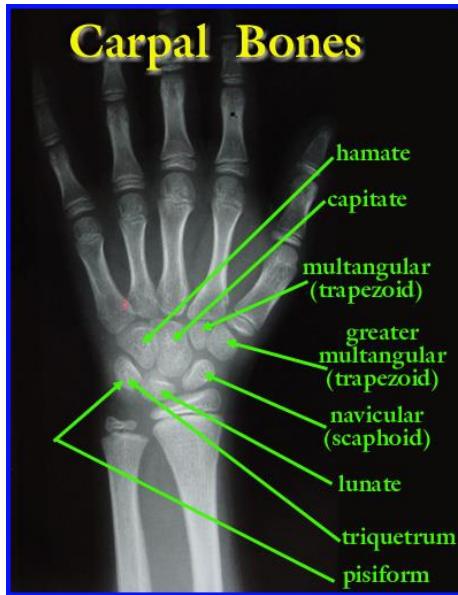

Scaphoid Fracture

- Diagnosis: Scaphoid Fracture.

- Clinical Sign: Tenderness in the anatomical snuffbox.

- Management: Thumb spica splint/cast. If X-ray is normal but tenderness is present, treat as a fracture and repeat X-ray in 10-14 days or order a CT/MRI.